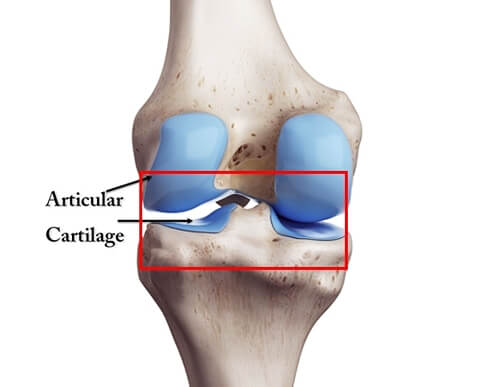

우리 몸에서 무릎, 어깨, 손가락, 손목, 고관절 등과 같이 뼈와 뼈가 만나는 관절은 평생 동안 굉장히 많은 움직임이 있기 때문에 뼈와 뼈의 충돌을 막는 연골이라는 성분이 존재합니다.

그런데 노화에 따라 연골이 달거나 운동선수처럼 단기간에 관절을 반복적으로 사용하는 경우에는 뼈와 뼈가 직접적으로 서로 충돌하게 되어 관절의 염증이 발생하게 되고 결국 만성적인 통증으로 이어지게 됩니다. 이것이 바로 우리가 흔히 말하는 '퇴행성 관절염'이라고 부르는 질환입니다.

그런데. MSM이라 불리는 식이유황은 관절의 연골과 인 조직을 구성하는 콜라겐 합성에 필수적인 성분이기 때문에 MSM을 섭취하면 관절의 연골과 인대 조직 재생에 도움이 될 수 있습니다.